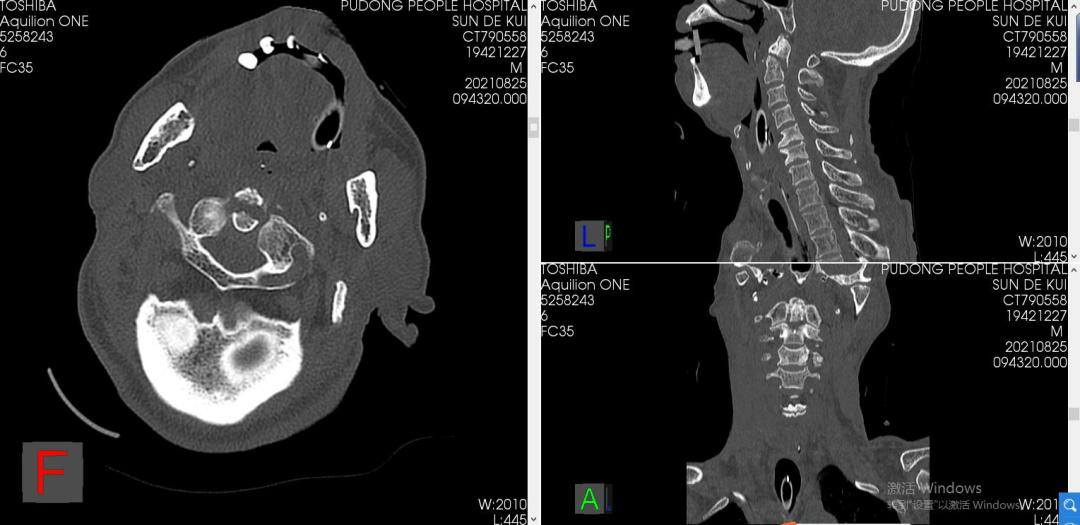

老王(化名)因车祸外伤后出现心跳、呼吸骤停,被送至浦东新区人民医院急诊创伤中心就诊。医务团队迅速对患者实施心肺复苏等急救措施,幸运的是,老王在鬼门关边缘几度徘徊后被终被救了回来,逐渐恢复了神志,但不幸的是,他显现了四肢截瘫症状,进一步检查确诊为枢椎齿状突骨折伴寰枢椎后脱位。近日,医院脊柱外科团队近日利用术中O-Arm 3D成像联合计算机辅助导航技术成功完成手术。

专家介绍,老王的情况很严重,此类型骨折脱位患者临床极其罕见,致死、致瘫率极高,手术难度大、风险高,是大多数脊柱外科医生不愿触碰的领域。急救团队待老王生命体征平稳后收入重症ICU监护治疗、并行颅骨持续牵引稳定齿状突骨折、复位寰枢椎脱位,同时脊柱外科团队接到会诊,脊柱外科主任王健第一时间组织讨论为患者制定了进一步的治疗方案。

为让患者术后保留更多的颈椎活动范围,手术团队最终放弃了风险相对较低的枕-颈融合术,而采用手术技术要求极高的寰-枢椎椎弓根钉内固定手术。在决定了治疗方案后,脊柱外科团队对患者进行了一系列术前准备工作,包括颈椎MRI检查、椎动脉CTA明确有无椎动脉解剖变异等。

在伤后1周,由骨科王健主任主刀为老王成功实施了C1-2椎弓根钉内固定手术。术中,O-arm成像同步计算机数字导航技术确保了椎弓根螺钉植入的精确性,缜密的术前计划和娴熟的手术技术保证了手术的顺利实施。整个手术过程中患者生命体征平稳,术后即刻解除了繁重的颅骨牵引,使用方便拆装的颈托辅助外固定。目前老王正处于术后恢复期,病情平稳,并在康复医师专业指导下进行康复训练。